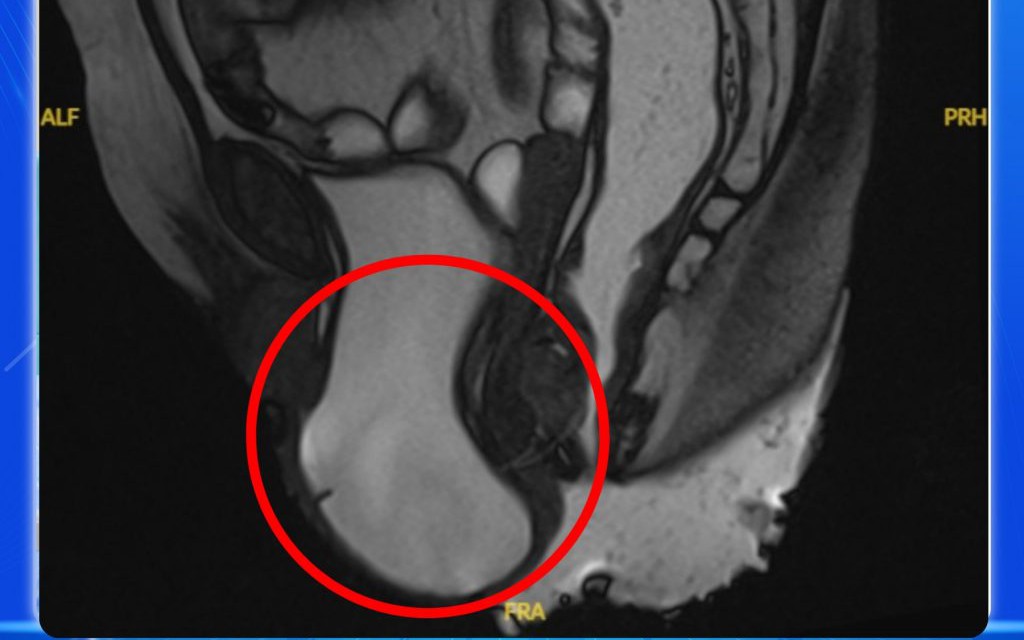

GĐXH - Người phụ nữ bị sa sàn chậu có biểu hiện rối loạn tiểu tiện như tiểu khó, tiểu phải rặn và đôi lúc tiểu són, khiến cuộc sống thêm phần nặng nề...